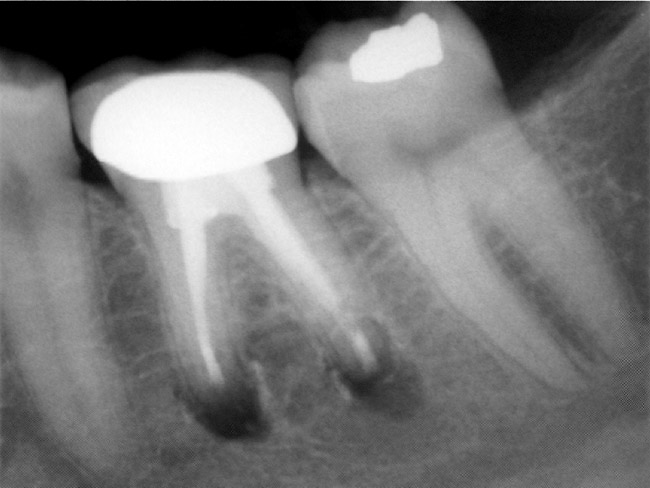

Figure 4e  The postoperative radiograph shows the re-treated tooth with 5 main canals.

Figure 4e

Figure 4f  The 1-year recall radiograph demonstrates the complete resolution of the periradicular radiolucencies.

Figure 4f